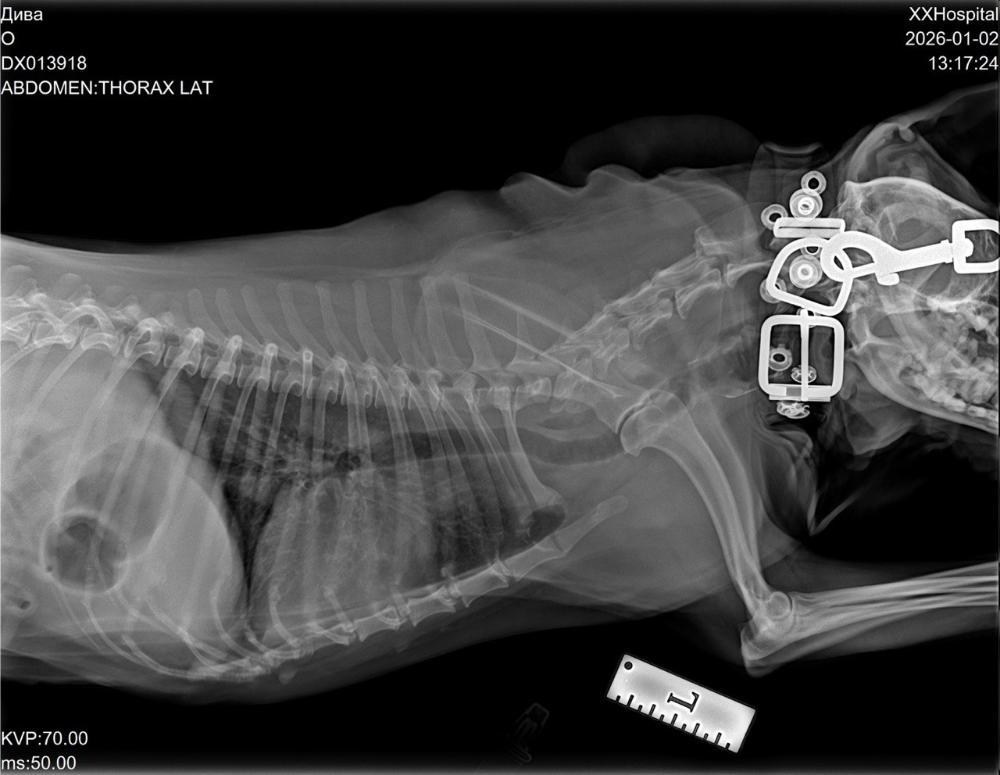

Результаты нашего посещения кардиолога.

Ввиду повышения СРБ -два варианта развития событий:

1. Курс а/ б доксициклин 14 дней, далее контроль ОКА, СРБ.

2. Плановая ЛТБС+ БАЛ

Реально я понимаю, что на второй вариант я буду собирать денежки очень долго, да ещё в теме минус(((

А начинать с чего-то надо, поэтому пьем доксициклин ( в наличии есть, благодаря вашим посылкам) , сдаём анализы - смотрим результат.

Помощь малышке Диве очень актуальна: помогите закрыть минус и собрать на анализы🙏🙏🙏